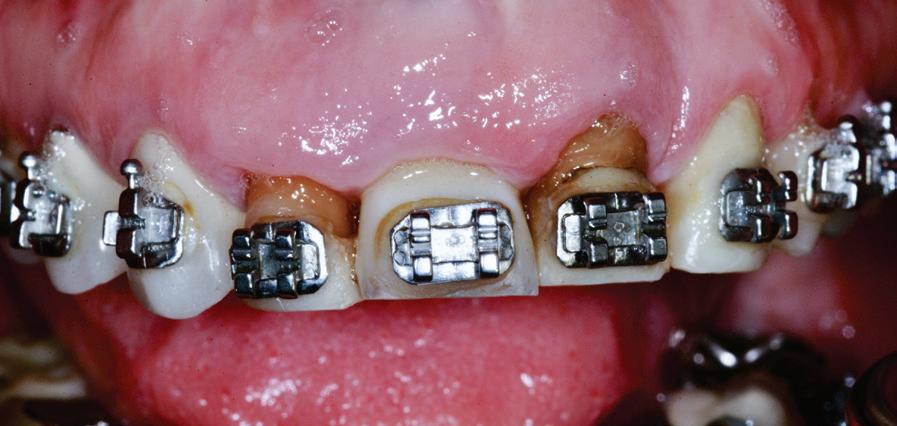

Un pacient caucazian în vârstă de 77 ani s-a prezentat la clinica autorului după cinci ani în care nu a fost la niciun control stomatologic. Examinarea clinică a arătat o pierdere semnificativă de os, parodontită cronică și multiple edentații care au destabilizat ocluzia. Pacientul a raportat sensibilitate la rece la nivelul primului molar drept inferior nr. 46, în special la ingerarea de lichide reci. Radiografia periapicală a confirmat constatările examenului clinic; în

plus, s-a detectat și prezența unei carii radiculare la nivelul rădăcinii distale a aceluiași molar, cu răspuns pozitiv la testul de sensibilitate (fig. 1-2).

1. Situația clinică inițială.